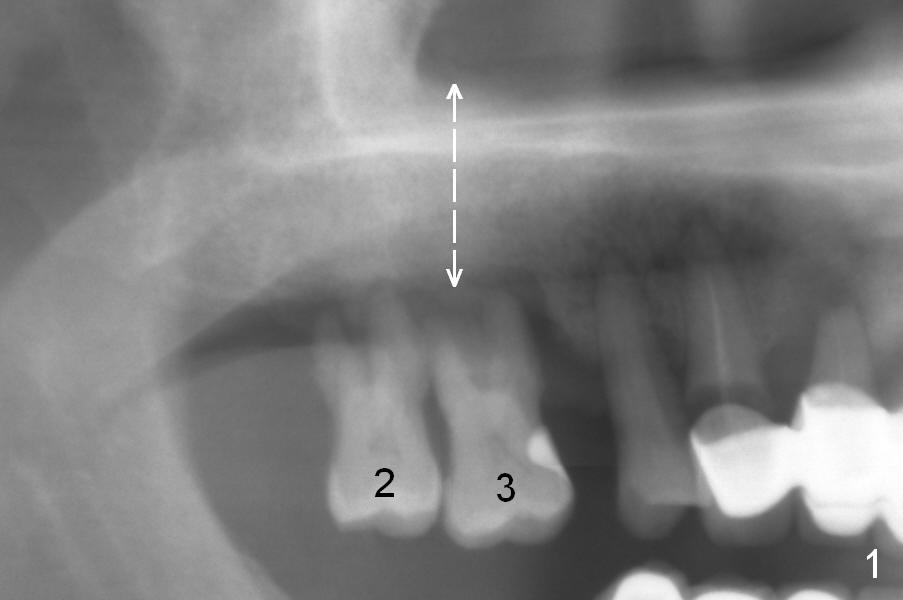

The maxillary 1st molar has 3 widely separated roots (Fig.1-3: #3) with a wide septum in between, as compared to the 2nd one (#2). The septum is a suitable site of immediate implant. When the septum is destroyed by pathology, the immediate implant has to be big.